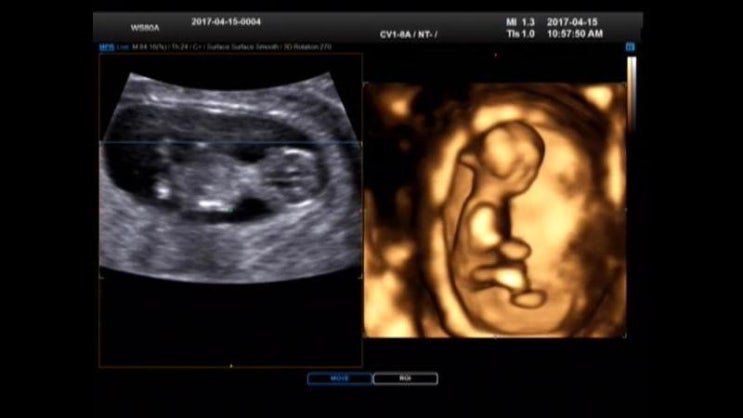

[둘째 임신주수별 진료]1차기형아검사 입체초음파 ☆임신11주6일☆ 2017.04.15

둘째 임신주수별 진료 1차기형아검사 입체초음파 임신11주6일 2017.04.15 1차기형아검사~~ 입체초음파로 아...